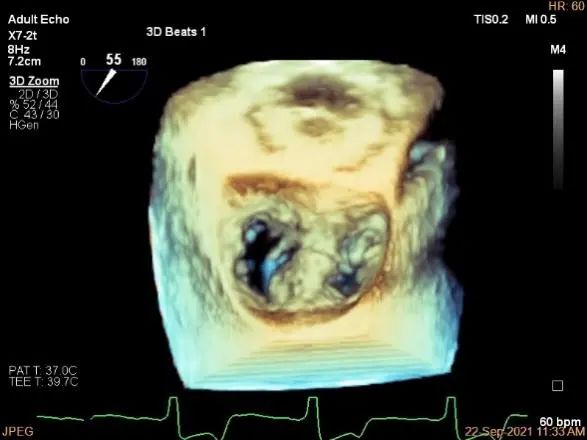

术中超声

P2区脱垂,宽14.8mm,Gap:3.3mm

三维评估两个夹子位置

3D:P1区脱垂并腱索断裂,Width:11.4mm